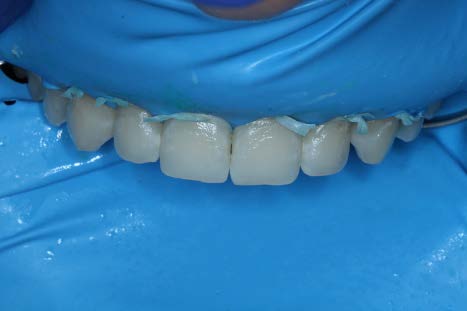

After rubber dam placement, the HCl Icon Etch was applied for 2 minutes.

After a second 2 minute application of HCl etch, the Icon Dry alcohol solution was applied to check for visual improvement (not pictured). Most lesions appeared camouflaged at this point other than teeth #7 and #11. So a third round of etching was performed.